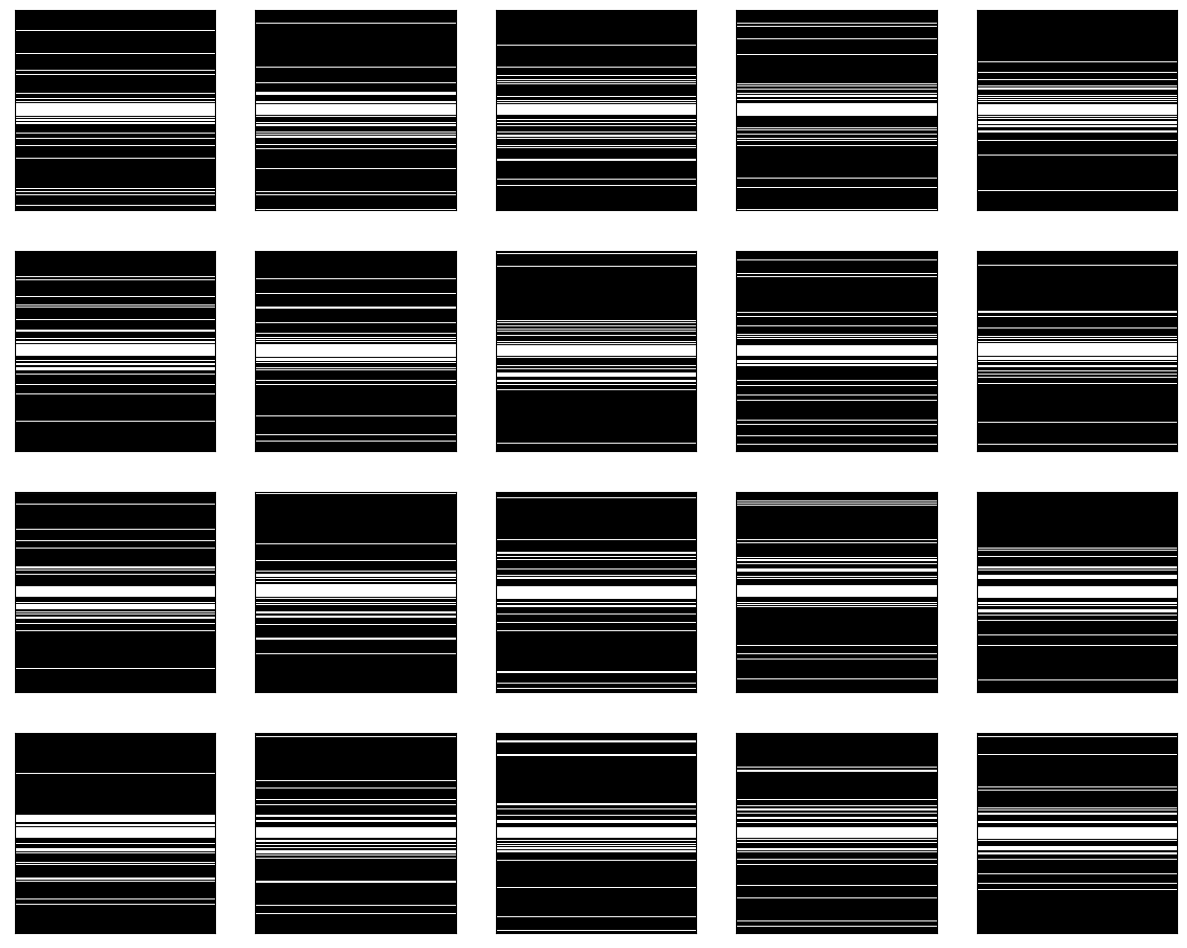

imsshow(mask[0, :, :, :], num_col=5, cmap='gray')The output is in Graph 1.1. We can clearly see that the undersampling mask for dynamic frames differs.

| Graph 1.1 undersampling mask for different dynamic frames |